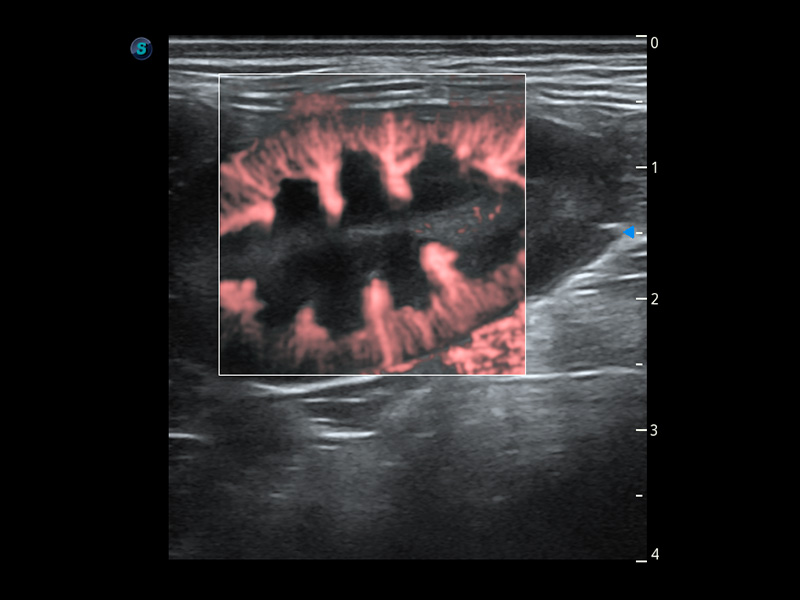

ProPet 60 作为一款高端台式动物超声设备,为动物医生的日常诊断提供了一系列贴合动物临床需求、解决临床实际问题的高级成像功能。凭借全系列高清探头,满足医生对腹部、心脏、生殖、浅表、肌骨等成像的所有需求,切实帮助您提升检查效率,提高诊断信心。

动物是人类最亲密的朋友和最值得信赖的伙伴。米兰官方网站也一直致力于探索动物专用的超声影像解决方案。 全新推出的ProPet系列,是米兰官方网站在动物超声影像智能化、专业化、精准化的一次跨越式革新。动物不能用言语来表述自己的不适,通过超声影像,ProPet系列搭建了动物医生与不同物种沟通的“桥梁”,为动物医生注入了“治愈之力”。